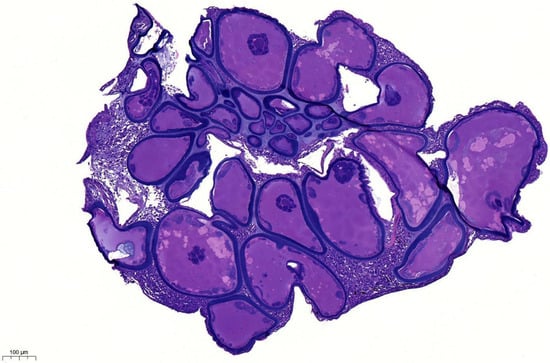

Although the clinical course and pathogenesis of lymphocystis disease virus (LCDV) infection have been extensively described in freshwater and seawater environments, lymphocystis disease has not been studied in the copperband butterflyfish (Chelmon rostratus) or described at the molecular level in orbicular batfish (Platax orbicularis). The present study aimed to identify LCDV in a copperband butterflyfish and an orbicular batfish using light and electron microscopy (morphological) and molecular methods, namely PCR followed by phylogenetic analysis. We present a case series of two representatives of two distinct fish species with stress-induced chronic LCDV infection, which presented with typical, recurring, macroscopically visible lymphocystis nodules on their pectoral, caudal, and dorsal fins. After collecting lymphocystis nodules from live animals using skin scraping, we processed the hypertrophic giant cells for qualitative analysis using light and electron microscopy. Through our qualitative morphological analysis, we also share intimate observations of putative viral replication and assembly in the intracytoplasmic inclusion bodies of lymphocystis nodules. We present LCDV infection in a novel species, the copperband butterflyfish, and our molecular analysis identified the virus from the orbicular batfish as a novel LCDV species. Full article

Show Figures

Figure 1